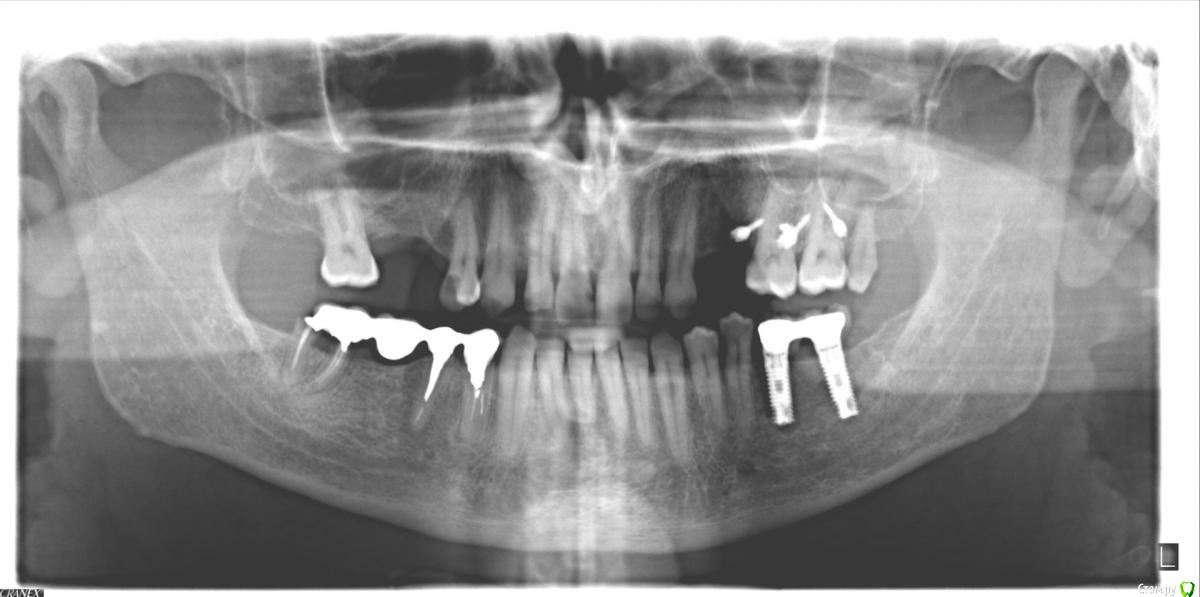

LK9722 Опубликовано 20 февраля, 2015 Автор Поделиться Опубликовано 20 февраля, 2015 самый свежий снимок, декабрь 2014 года с уже отколовшимся кусочком 7-ки и новыми только что вкрученными нижними имплантами Ссылка на комментарий

shishok Опубликовано 22 февраля, 2015 Поделиться Опубликовано 22 февраля, 2015 1)кариес на 27 зубе начался на задне-пришеечной поверхности(не сверху).Его видно на втором панорамном снимке.26 зуб рентгенологических признаков кариеса не имеет.2)восьмой удалить!3)по рг-снимку кариеса на 16 зубе нет,но нужно смотреть очно.4)по имплантам не подскажуя.т.к. я-терапевт.5)если 14 зуб беспокоит,то лучше перелечить.6)а 46 зуб нужно было удалять давним-давно(судя по первой ОПТГ).Вопрос о сроке службы моста на данный момент уже чисто риторический Ссылка на комментарий